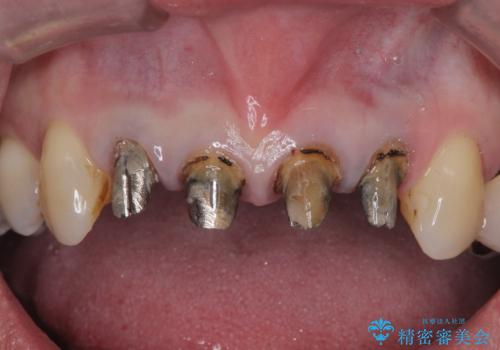

- 「黒ずみの前立つ前歯をやりかえ、きれいにしたい。」と希望され来院されました。

金属色の目立つ前装冠を除去し、発生していた小さな虫歯を丁寧に全て除去しジルコニアセラミッククラウンで審美的な前歯となるような治療を計画します。

- 44万円(仮歯・ジルコニアクラウン×4)費用は治療当時の料金となります